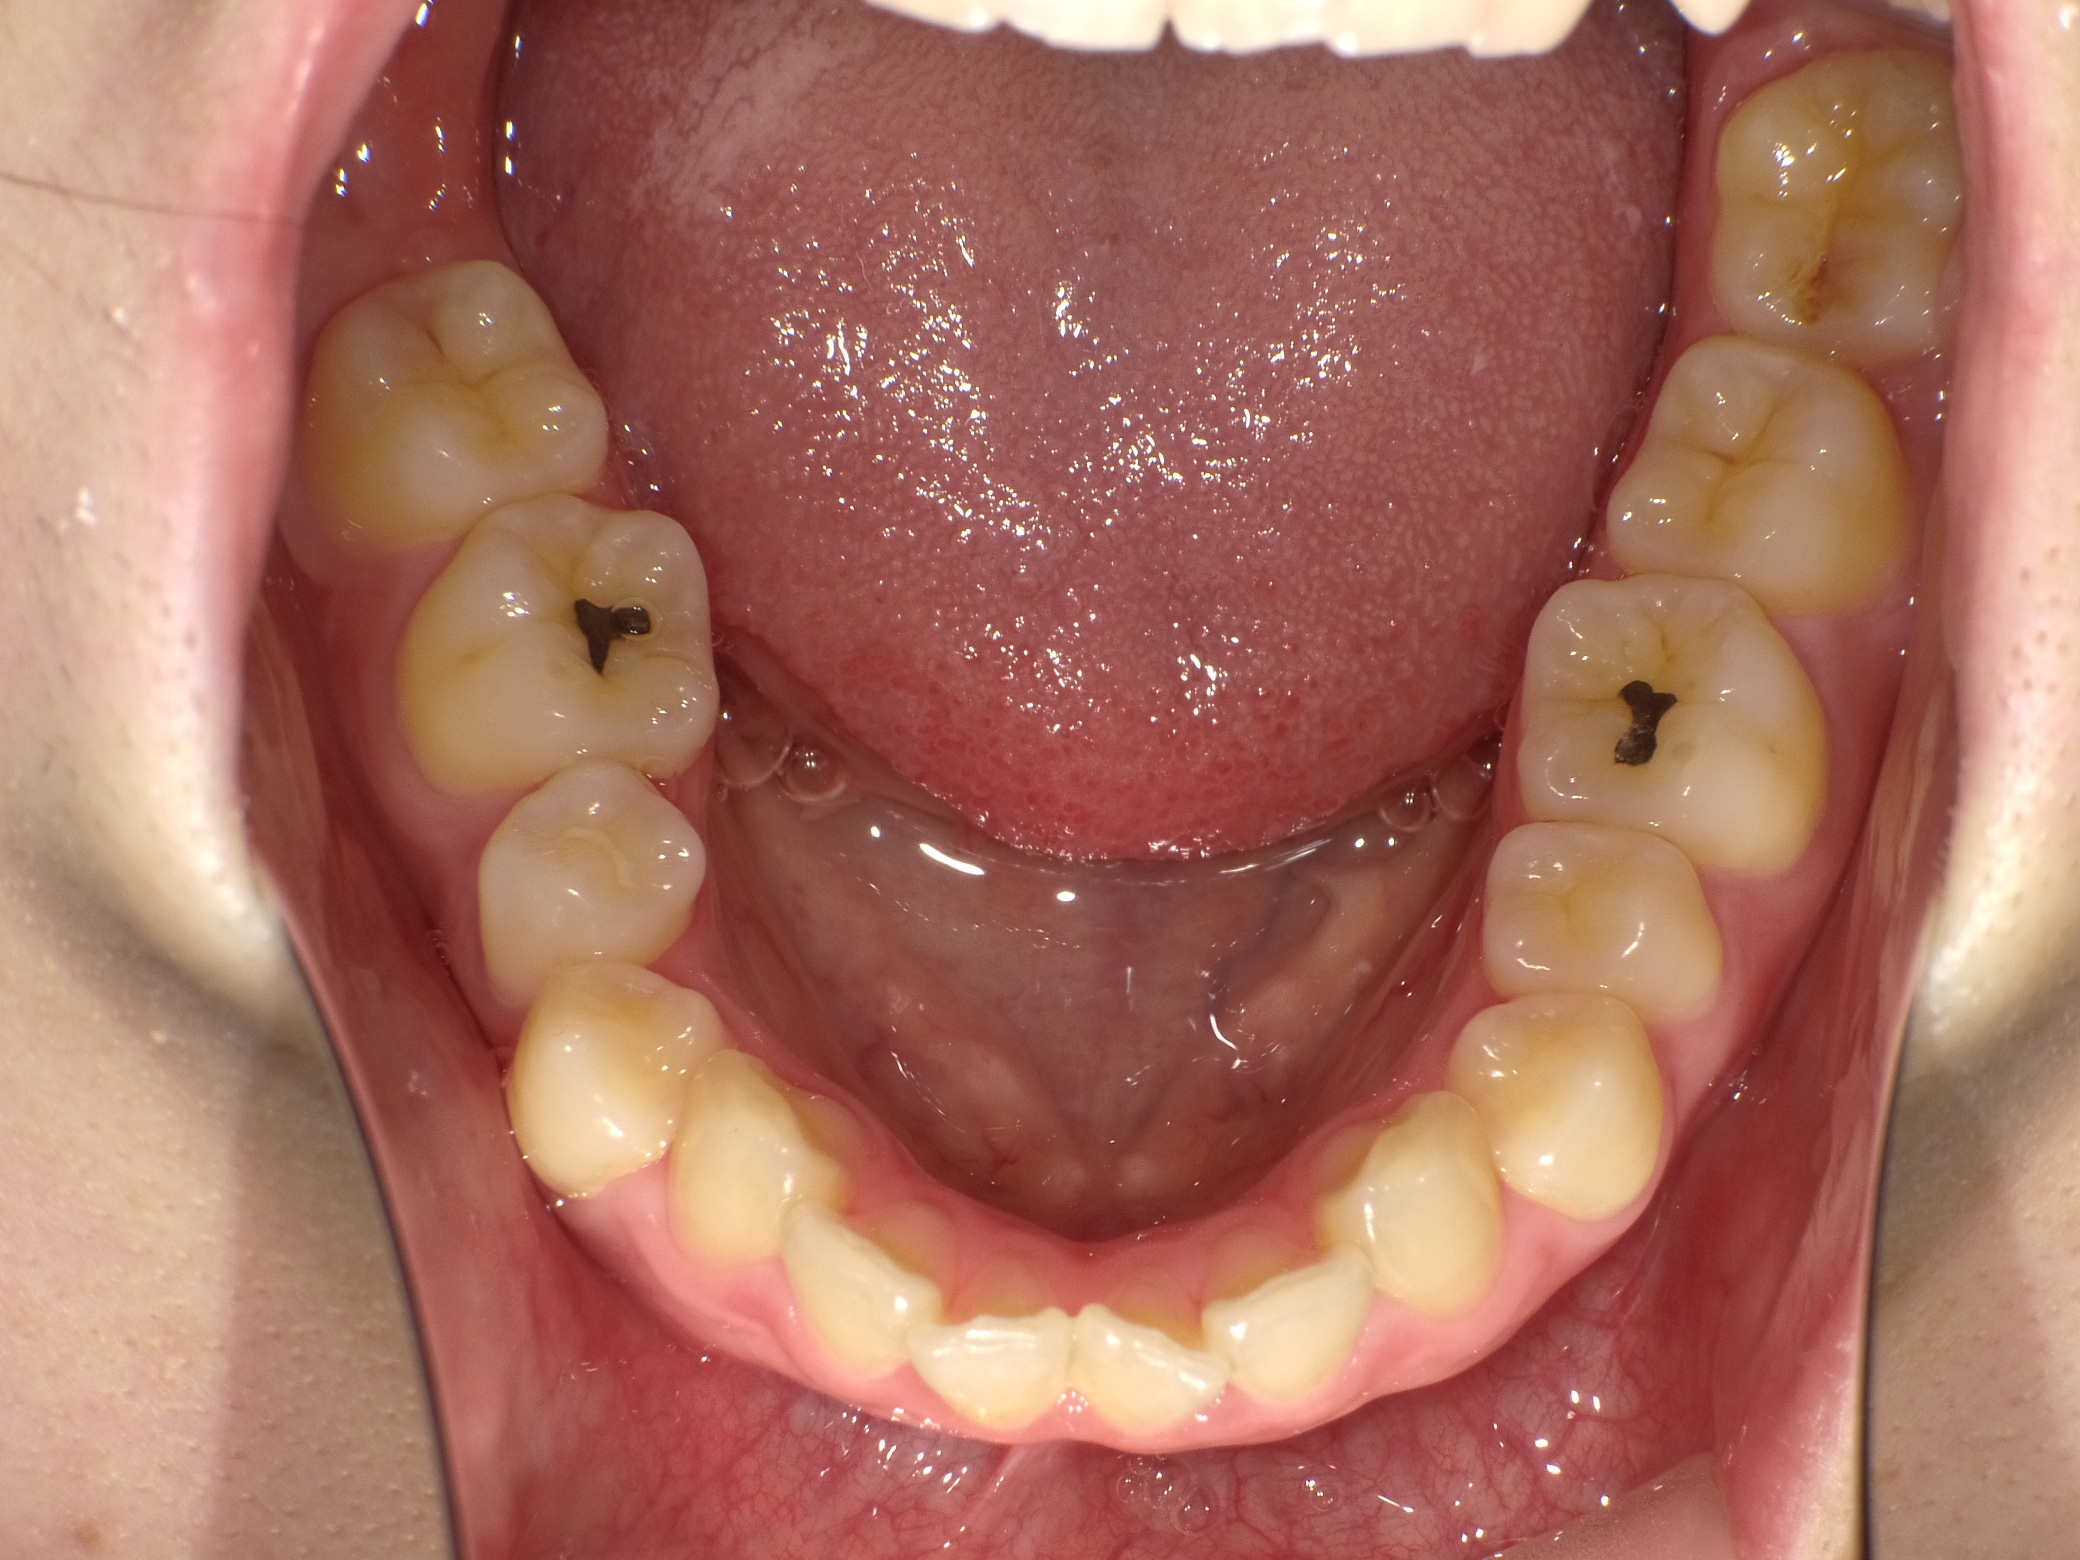

口内下

治療前

治療後

上の前歯に重なりがあることと口元が前突していることが問題となっていました。

上の前歯は唇側に傾斜しており、全体的に手前に倒れるような歯の配置となっていました

検査の結果、傾斜を治し、口元を内側に引き込むため、上下の歯を抜いてワイヤー装置で歯を並べることとしました

抜歯によって得られたスペースを十分に活かすことで、上の前歯の重なりと、口元の前突感、全体的な歯の傾斜を改善することが出来ました。